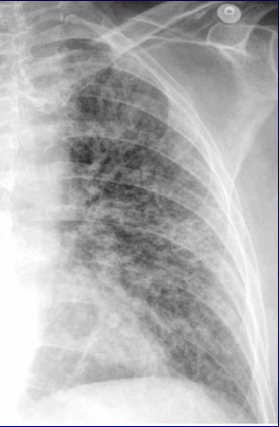

Fibrose pulmonaire : approche diagnostique et cas cliniques

• Fibrose pulmonaire  approche diagnostique et cas cliniques